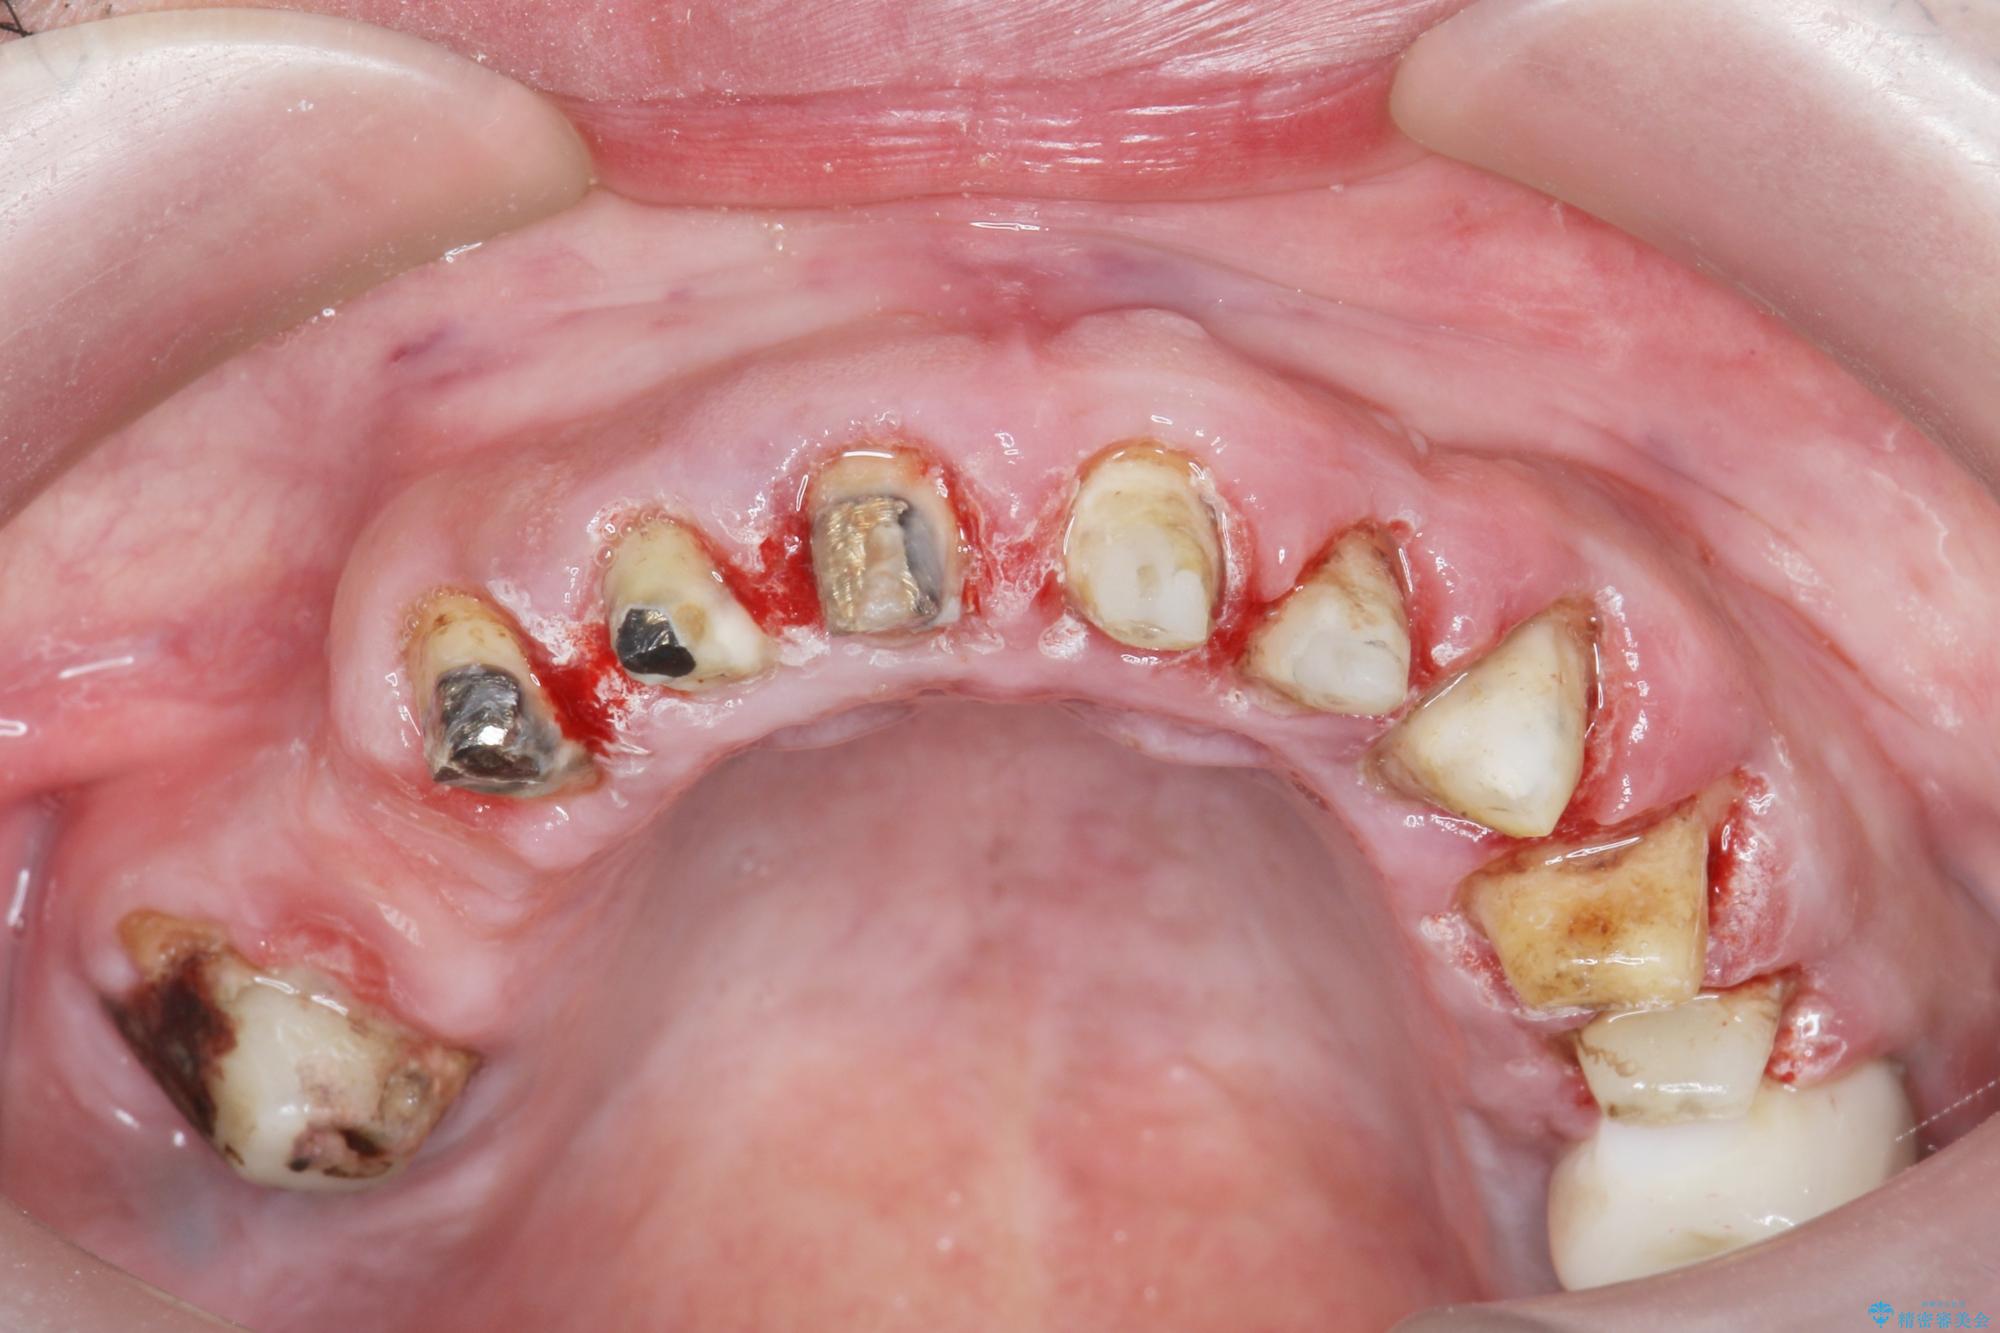

歯周組織検査を行うと歯ぐきからは容易に出血し、X線検査より歯とセラミッククラウンの適合が悪い(ピッタリと合っていない)状態が示唆され、歯ぐきの炎症を惹起している状態でした。

セラミッククラウンを除去し仮歯を装着し、歯周外科手術を行い歯ぐきの状態を改善したのち、適合の良いセラミッククラウンを再作製をする治療計画としました。